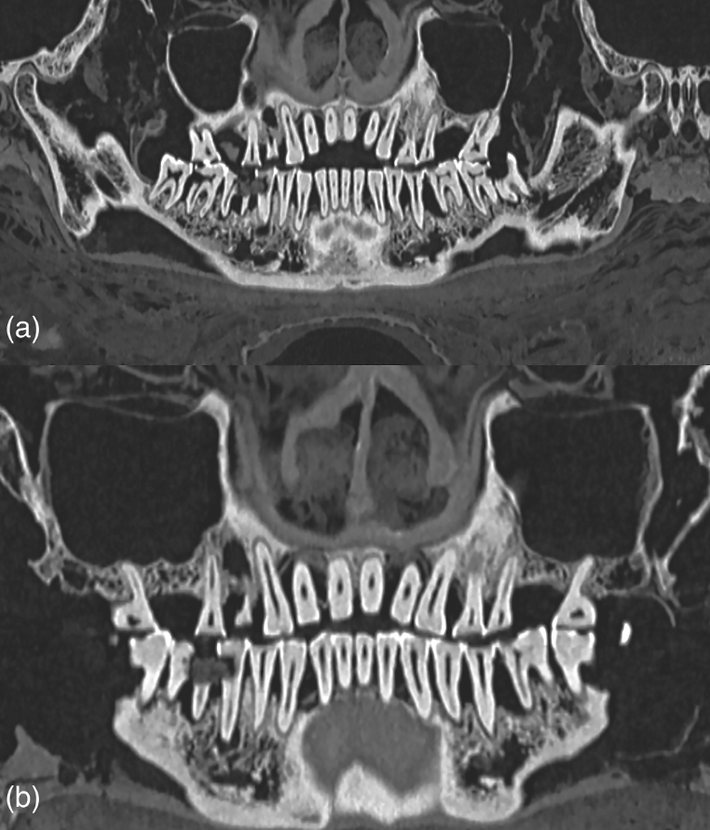

Để có được kết luận này, các chuyên gia đã sử dụng kỹ thuật chụp cắt lớp vi tính (CT) để mô tả đầy đủ về răng xác ướp Ai Cập. Ảnh: @Bảo tàng Khảo cổ học Quốc gia Athens.

Các nhà nghiên cứu đã tìm thấy một khoang xốp trong răng của xác ướp này chứa đầy vật liệu trám bảo vệ. Ảnh: @Bảo tàng Khảo cổ học Quốc gia Athens.